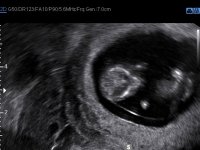

Tatt når jeg var 6+5